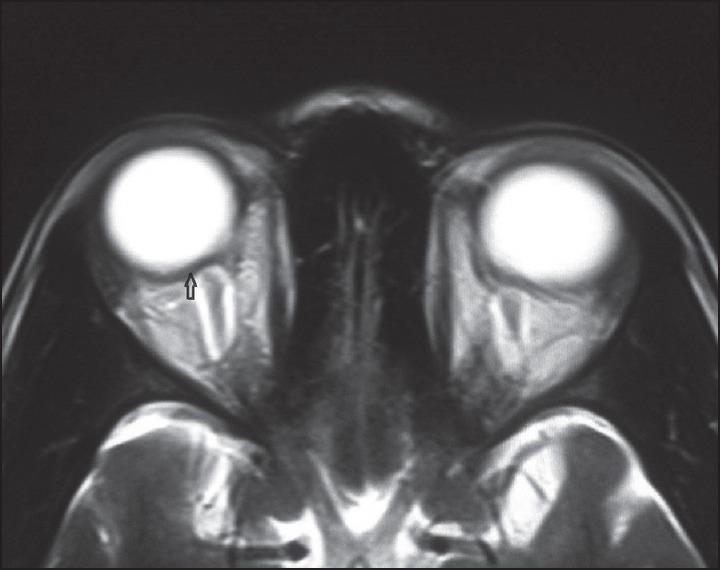

Idiopathic intracranial hypertension (IIH) is a disorder defined by clinical criteria that include signs and symptoms isolated to those produced by increased intracranial pressure (ICP; e. g., headache, papilledema, and vision loss), elevated ICP with normal cerebrospinal fluid (CSF) composition, and no other cause of intracranial hypertension evident on neuroimaging or other evaluations. The most common signs in IIH are papilledema, visual field loss, and unilateral or bilateral sixth cranial nerve palsy. Here we report a case of IIH presenting as headache with vision loss, papilledema, complete ophthalmoplegia with proptosis in one eye, and sixth cranial nerve palsy in the other eye. Patient was managed with acetazolamide, topiramate, and diuretics. Symptoms remained static and she was planned for urgent CSF diversion procedure.